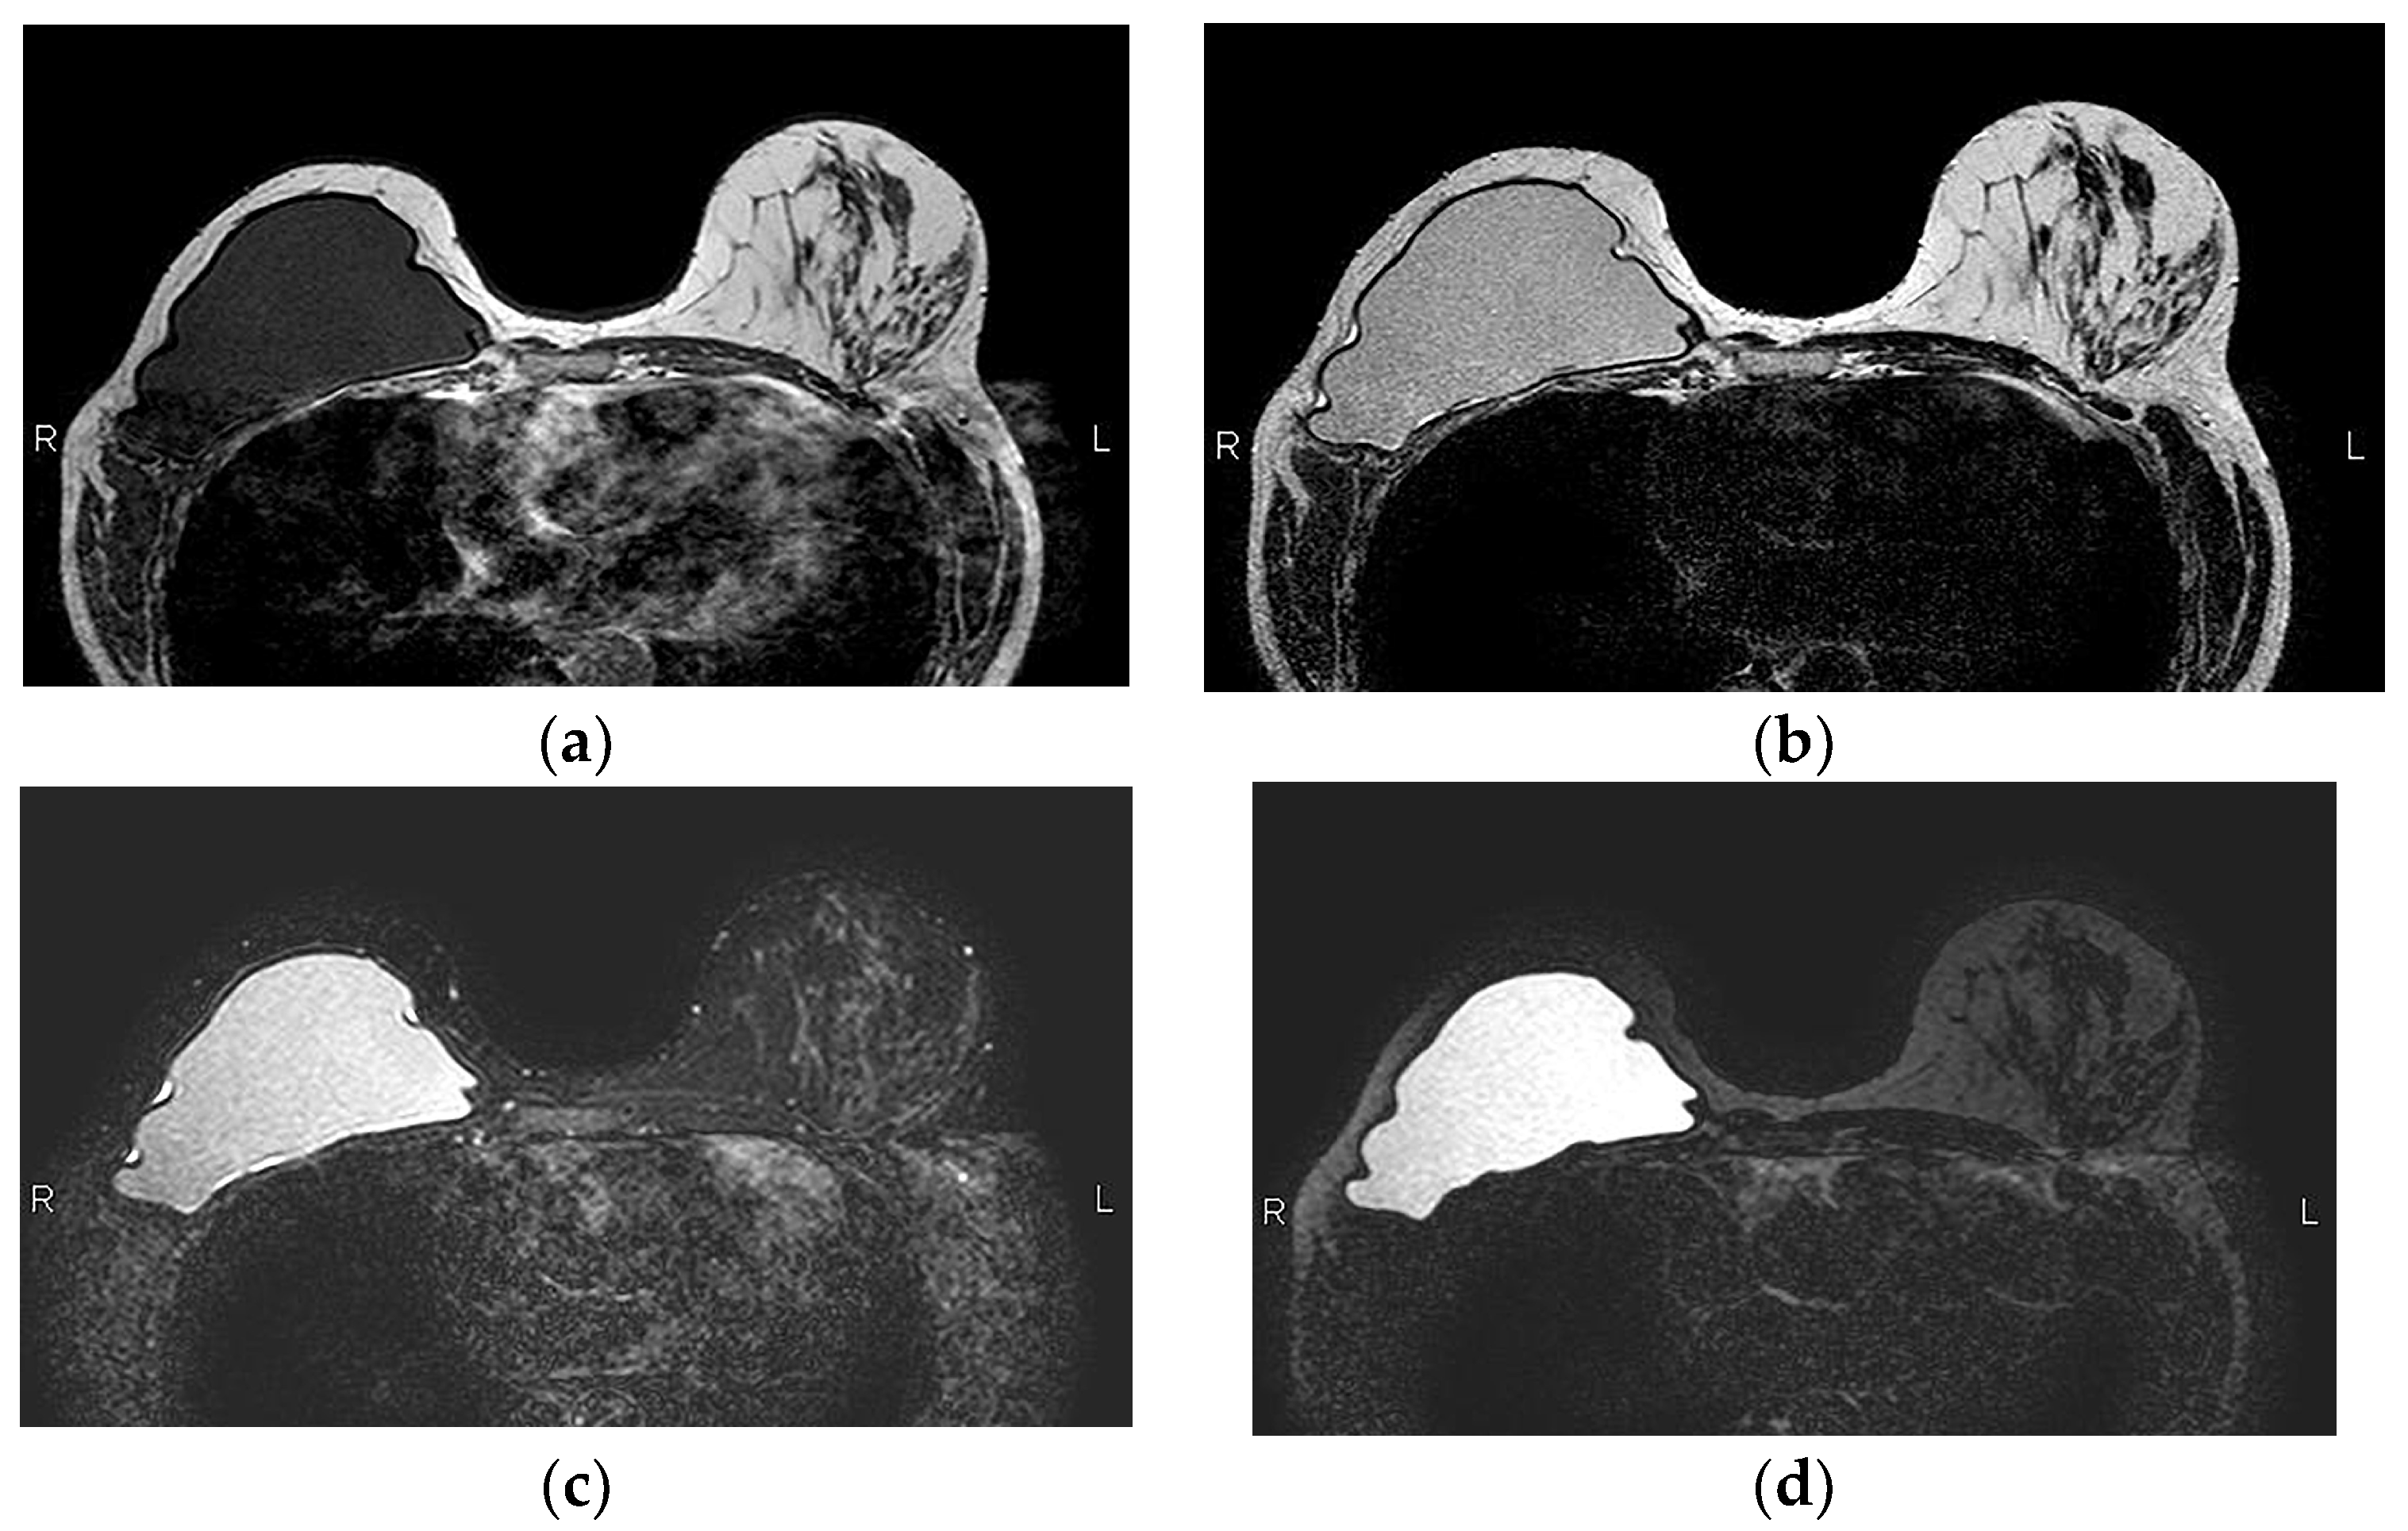

5.2.5. Implant Rupture

- Wong, T.; Lo, L.W.; Fung, P.Y.; Lai, H.Y.; She, H.L.; Ng, W.K.; Kwok, K.M.; Lee, C.M. Magnetic resonance imaging of breast augmentation: A pictorial review. Insights Imaging 2016, 7, 399–410. [Google Scholar] [CrossRef] [PubMed]

- Norena-Rengifo, B.D.; Sanin-Ramirez, M.P.; Adrada, B.E.; Luengas, A.B.; Martinez de Vega, V.; Guirguis, M.S.; Saldarriaga-Uribe, C. MRI for Evaluation of Complications of Breast Augmentation. Radiographics 2022, 42, 929–946. [Google Scholar] [CrossRef]

- Seiler, S.J.; Sharma, P.B.; Hayes, J.C.; Ganti, R.; Mootz, A.R.; Eads, E.D.; Teotia, S.S.; Evans, W.P. Multimodality Imaging-based Evaluation of Single-Lumen Silicone Breast Implants for Rupture. Radiographics 2017, 37, 366–382. [Google Scholar] [CrossRef] [PubMed]

- Safvi, A. Linguine sign. Radiology 2000, 216, 838–839. [Google Scholar] [CrossRef]

- Soo, M.S.; Kornguth, P.J.; Walsh, R.; Elenberger, C.; Georgiade, G.S.; DeLong, D.; Spritzer, C.E. Intracapsular implant rupture: MR findings of incomplete shell collapse. J. Magn. Reson. Imaging 1997, 7, 724–730. [Google Scholar] [CrossRef] [PubMed]

- Maijers, M.C.; Niessen, F.B.; Veldhuizen, J.F.; Ritt, M.J.; Manoliu, R.A. MRI screening for silicone breast implant rupture: Accuracy, inter- and intraobserver variability using explantation results as reference standard. Eur. Radiol. 2014, 24, 1167–1175. [Google Scholar] [CrossRef]